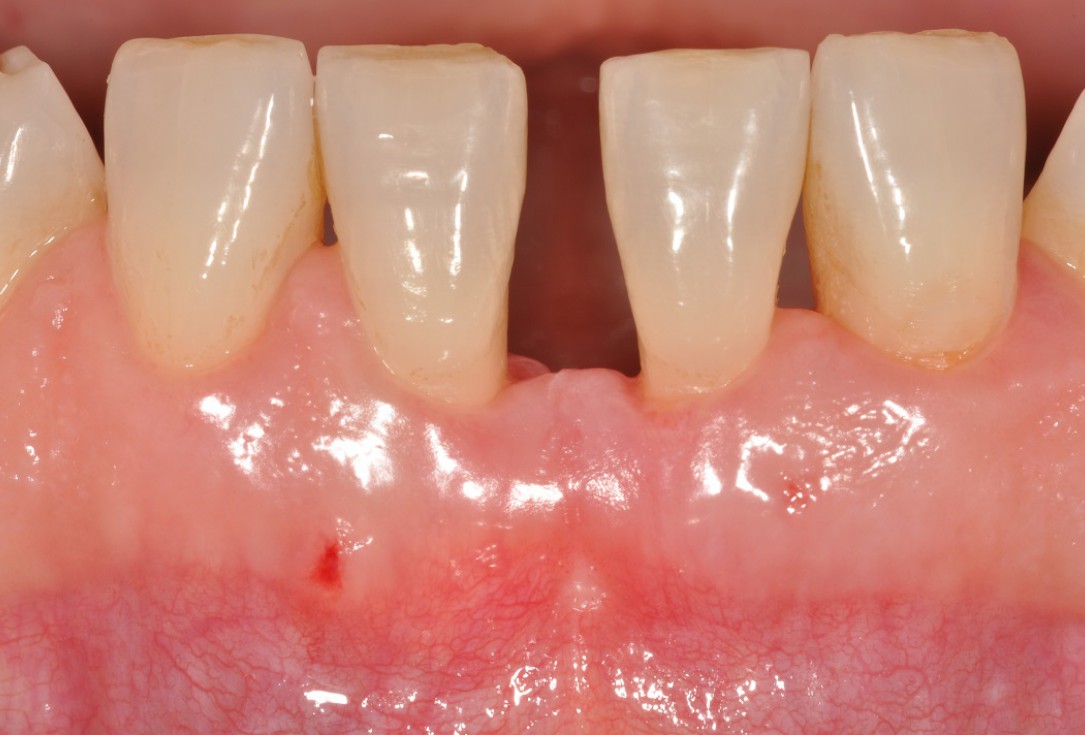

01/13 - Baseline clincial situation and pre-surgical probing.

Wide intrabony defect treated with the modified papilla preservation flap in conjunction with Straumann® Emdogain® and autogenous bone - Dr. B. Molnar